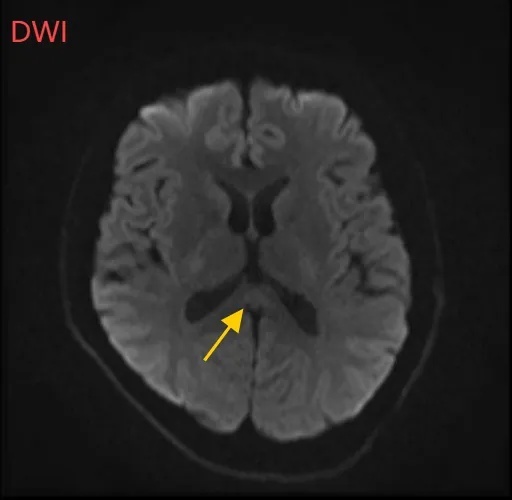

医师摇摇头,通过头部磁共振平扫、弥散、增强印象等查看,医师确诊,小董是得了一种比较罕见的病症:可逆性胼胝体压部归纳征。。

小董的印象成果显现,胼胝体压部产生病变。

假如把大脑比作一座城市,胼胝体便是衔接左右脑的“跨海大桥”,而胼胝体压部正是桥上的“中心纽带”。当它因酒精、熬夜或感染“肿了”,大脑信号就会“堵车”,引发一系列“毛病”。

“压部”病变。:胼胝体压部是大脑里的“视觉总监”,眼睛所看到的信息传送到大脑后,由它担任反响整合成图像在脑海中呈现。“压部”产生病变后,就像电视机信号接纳不良,屏幕呈现雪花相同,眼睛视物就会受到影响。

除了“压部”,胼胝体的其他部位也有病变,所以小董才会呈现幻听、手抖等症状。

胼胝体压部病变普遍认为或许与细胞毒性水肿有关,而水肿的诱因一般是由于很多喝酒后导致维生素B1摄入妨碍,辅酶缺少。

通过一周医治,小董的胼胝体压部病变明显好转。